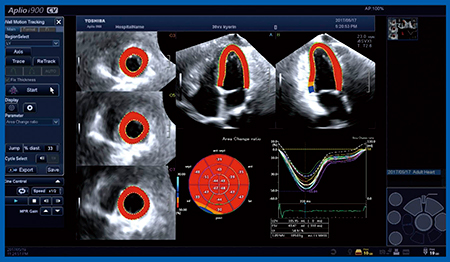

今回,Aplio iシリーズにてOn-lineで3D-WMTによる解析を行う画像描出の検討を行った。従来,右室のトラッキング評価の際には必ず右室が中心にくるように画像撮像をしていたが,今回は左室・左房・右室・右房の四腔全体を含めて撮像し,同一心拍の四腔それぞれの3D-WMTの解析を行う“Quad Chamber Tracking (QCT)”により右室のトラッキング解析も行った。実際の解析結果(図7)を見ると,右室は流入路,流出路ともに描出されており,トラッキングも良好で,RVEFやGlobal RV-ACRの値も得られた。また,Global RV-ACRは,心臓カテーテル検査における肺血管抵抗(PVR)や平均肺動脈圧(mPAP)と良好な相関が認められた。ただし,Global RV-ACRは右室全体の評価であり,局所の状況は不明であった。そこで,3D-RV WMTにて右室を7セグメントに分割し,それぞれのストレインカーブから右室の流入路(3セグメント),心尖部(2セグメント),流出路(2セグメント)の平均ACRを算出すると,健常者25例では流入路のACRが最も大きく−30%であり,流出路は−19%,心尖部は−20%であり,ACRはそれぞれの領域で異なることが明らかになった。また,健常者25例とPAH 50症例のACRを見ると,右室の流入路,心尖部,流出路のいずれにおいてもPAH症例の方が有意差をもってACRの絶対値が小さく,右心機能評価においては,今後,局所それぞれの領域をおのおの評価していくべきと考えられる。

図7 On-lineによる右室の3D-WMT解析結果